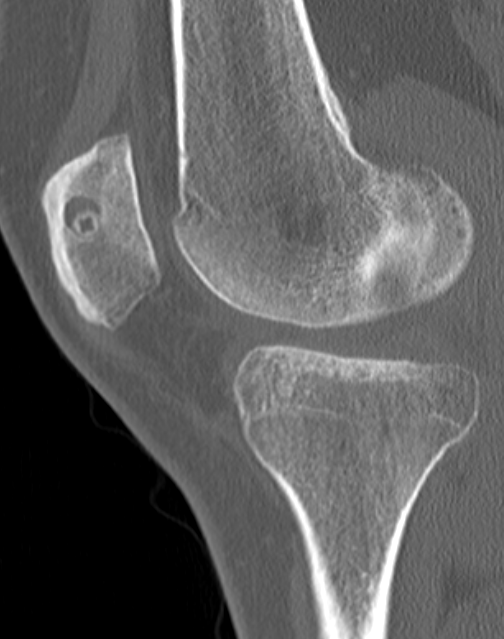

2. Perform TTT (if TTTG > 20)

- incision over TTT

- medialise at least 1 cm

- ensure some element of Fulkerson / anteriorise

- can distalise if patella alta

- secure with screws (2 x small fragment usually sufficient)

- reassess stability